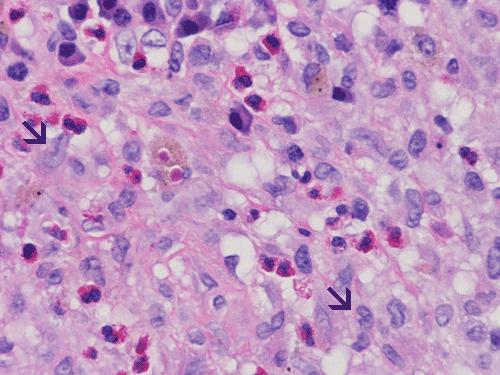

At scanning magnification (Panel A), the lung parenchyma is replaced by some coalescing fibrous nodules. The degree of involvement is variable at different fragments (Panel B and C). In the less affected areas, there are some fibrotic thickening of the septa (Panel C). In some areas, the changes are minimal and the pleural appear to be uninvolved (Panel D and E). In low to medium magnifications, these nodules of fibrosis contains a large number of hemosiderin laden macrophages (Panel F and G) admixed with fibrous tissue. The diagnostic tissue, however, is present in areas with increased cellularity. In these areas, there is a background of cells with a moderate amount of cytoplasm and bland nuclei. Some of these nuclei have kidney shape (arrow in Panel H). In some areas, many of the nuclei have a deep nuclear groove that resemble a coffee bean (arrow in Panel I). In the third type of areas, the nuclear grooving is not distinct (Panel J). Prominent eosinophilic infiltrations are almost always present. Immunohistochemistry on CD1a revealed many positive cells (Panel L). Also present in the specimen are multiple small blood vessels with thickened intima (Panel K). A Movat pentachrome stain demonstrates an internal elastic layer in these vessels and confirms that these are arteries (Panel M and N).

Pathologically, PLCH can be broadly divided into an early or cellular stage and a late or fibrotic stage. Demonstration of LCs is of critical importance for a correct diagnosis. The morphology of LCs is similar to LCH in other organs. LCs are characterized by a deep nuclear groove which lead to “coffee bean-shaped” or “kidney-shaped” nuclei. In most cases, the level of atypia and pleomorphism is low. A moderate amount of amphophilic to weakly eosinophilic cytoplasm is present. The cytoplasmic membrane is indistinct. Eosinophils and chronic inflammatory cells, varying from scant to abundant, are present. Except for a scant frankly pleomorphic cases, the level of pleomorphism and atypia is minimal to low. Eosinophilic abscesses with central necrosis may be present. Immunohistochemically, LCs are similar to their normal counter parts and are positive for CD1a and S100. At the ultrastructural level, Birbeck granules can be demonstrated. For most cases, the diagnosis can be established by histopathologic criteria but these additional features help to confirm the diagnosis.

In the early stage of PLCH, there are interstitial infiltrates composed of LCs, lymphocytes, macrophages, eosinophils, plasma cells and fibroblasts 4. The infiltrates enlarge to form nodules centered on the small airways. Brown pigmented macrophages (smokers macrophages) are present in and around the nodules. Eosinophils tend to localize at the innermost layer of the nodules, where LCs can be most easily found in the thickened interstitium. Associated patchy interstitial and airspace organization or respiratory bronchiolitis may be present. Other smoking related changes are also common. Cavitation often occurs within the nodules which represents either an airway remenant or de novo cavitation as the inflammatory infiltrate enlarges. There is centripetal replacement of the nodules by fibroblasts which produce the classic stellate lesions of PLCH. As the disease progresses, the number of nodules, cavitary granulomas and fibrotic scars increase in number.